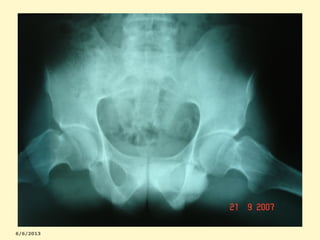

Graduação radiológica da SI

0=normal

3=sacroileite moderada

1=suspeita

4=anquilose óssea

2=sacroileite mínima

Esclerose marginal bilateral

Sacroieíte bilateral + sínfise púbica

ESCLEROSE + ALARGAMENTO +IRREGULARIDADE

Sacroileíte+sínfise+coxo-femurais

Sacroileíte bilateral com esclerose e

estreitamento das articulações sacro-ilíacas